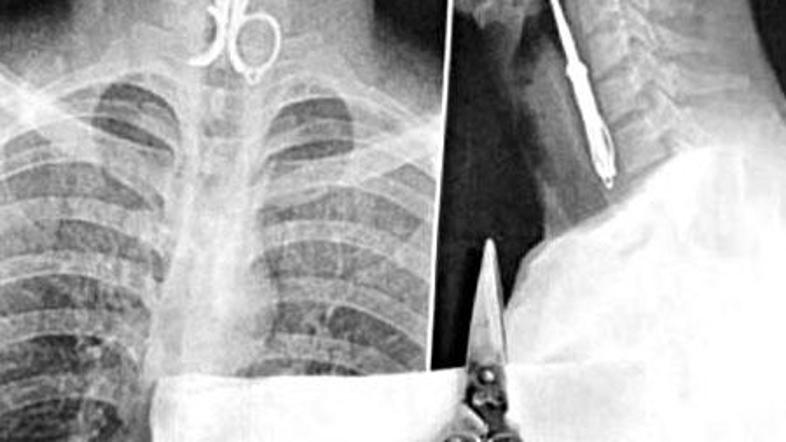

Ponesreči pogoltnil škarje

27-letnik je namreč med večerjo pogoltnil škarjice za nohte, s katerimi si je čistil zobe. Ko je nekdo med obrokom povedal šalo, se je Lin tako močno zasmejal, da so mu ponesreči spolzele iz rok in jih je požrl. Zadeva se je še dodatno poslabšala, ko je Lin poskušal škarjice izkašljati. Te so se mu zaradi tresljajev še bolj zarezale v požiralnik.

Nesrečnika so odpeljali v bolnišnico, kjer so mu pod lokalno anestezijo nenavadni zobotrebec odstranili. Na srečo ni utrpel hujših poškodb.